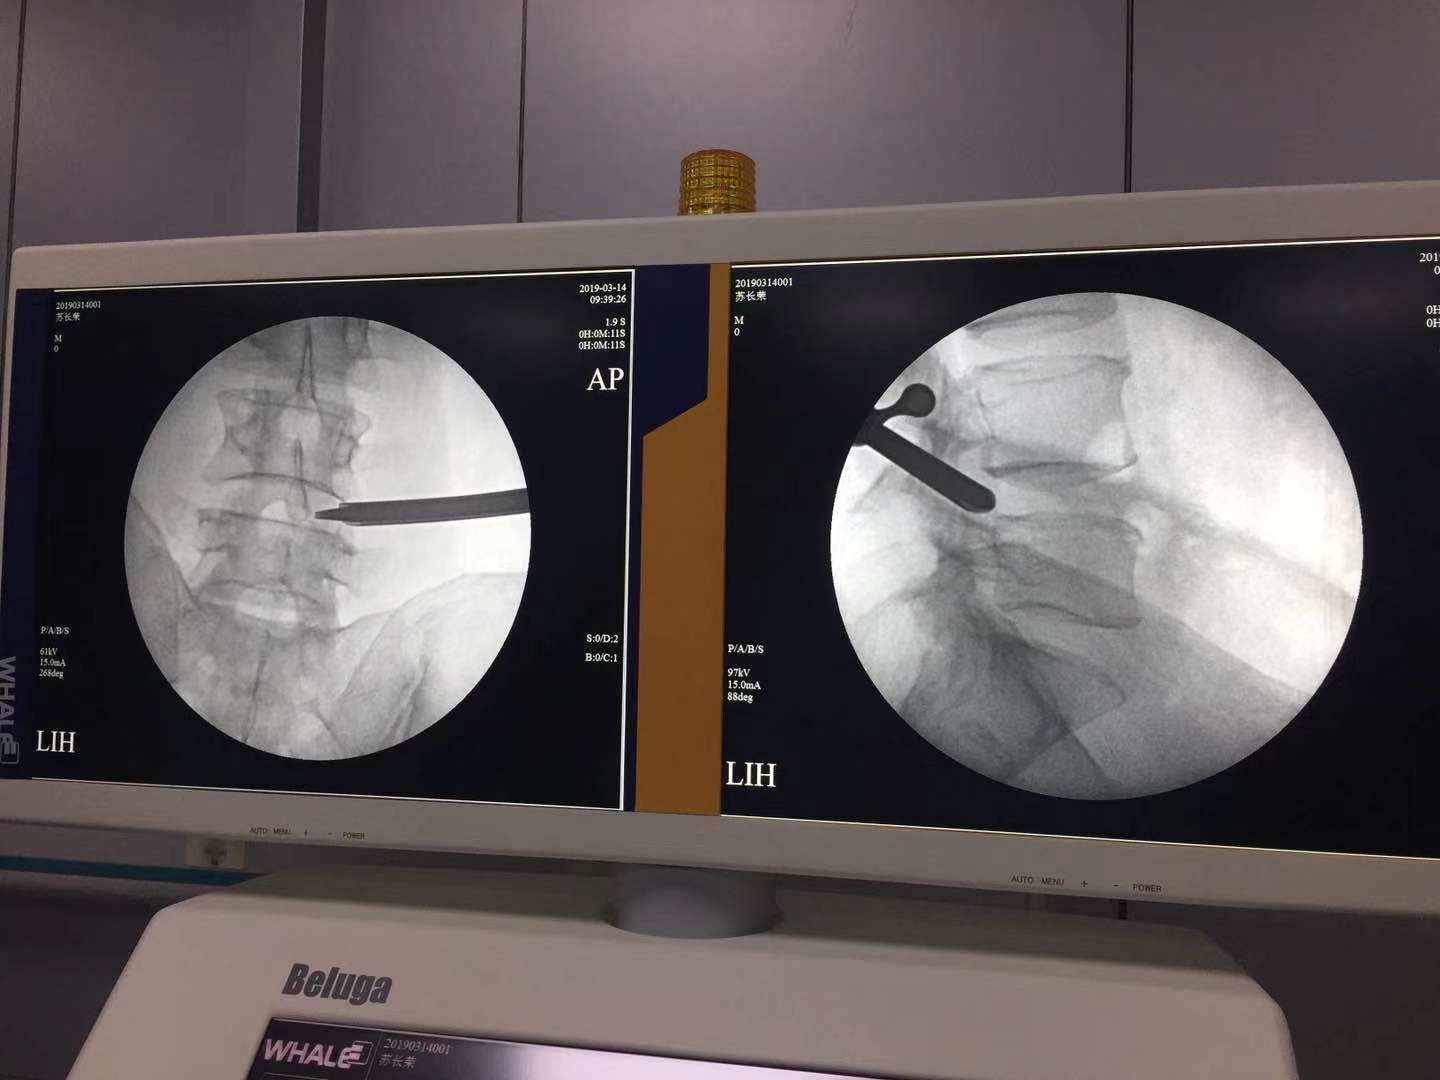

术中需要应用透视完成孔镜通道的建立

手术开始,患者采用俯卧位(脊柱科出身的大夫喜欢俯卧位,疼痛科出身的大夫喜欢侧卧位),麻醉后经过定位透视放置通道后的样子,因患者是局部麻醉,整个过程又是在透视引导下操作,相对来说风险较小,侧入路整个过程相对疼痛度低。